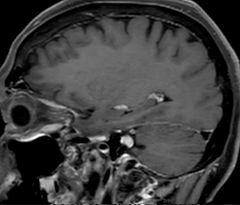

A two year follow-up scan of a CPA meningioma using both Ingenia 3.0T without CS and Ingenia Elition 3.0T with Compressed SENSE allows for a nice comparison to demonstrate the protocol improvements achieved on the Elition: 3D FLAIR has a shortened scan time, improved SNR and still the same spatial resolution. BrainView (3D T1 TSE) has improved spatial resolution and SNR with shortened scan time. For 3D T2 Drive the spatial resolution has been improved. 3D THRIVE used to have an interpolated 0.8 mm slice thickness, but true thickness at 1.6 mm, so that axial slices displayed a decent quality, but reformats were suboptimal.

Compressed SENSE is used on Elition to improve spatial resolution and reduce the non-interpolated slice thickness to allow smoothly reformatted images. Total scan time (adding SmartBrain and an additional b2000 diffusion) was 13:19 on Ingenia, and is now reduced to 10:42 on Ingenia Elition.

Ingenia Elition 3.0T with Compressed SENSE

3D T1w THRIVE (with Compressed SENSE)

3D T1w THRIVE

0.7 x 0.7 x 0.8 mm*

1:30 min.